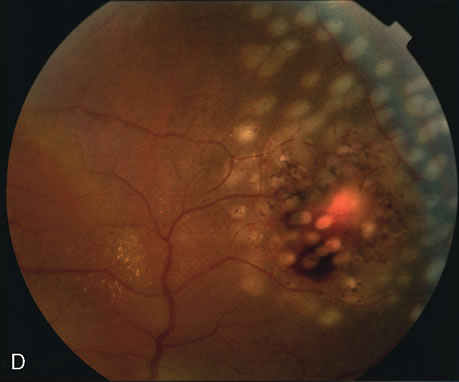

Fig. 16. Subfoveal, juxtafoveal, and extrafoveal choroidal neovascular membranes. A and B. Large subfoveal choroidal neovascularization (CNV) in a 69-year-old man with blood and pigment blocking central fluorescence on both the early-phase (A) and late-phase (B) photographs. The hypofluorescence surrounding the membrane is commonly seen in CNV and may be due to lipofuscin. C. Juxtafoveal CNV in a 37-year-old man with idiopathic CNVM. D. Cuticular drusen in same patient as in C were asymptomatic. E. Years later, this same patient developed a large extrafoveal CNV with central macular pigment abnormalities. A large neurosensory detachment was responsible for the disappearance of the drusen. (Courtesy of Dr. Kenneth G. Noble.)